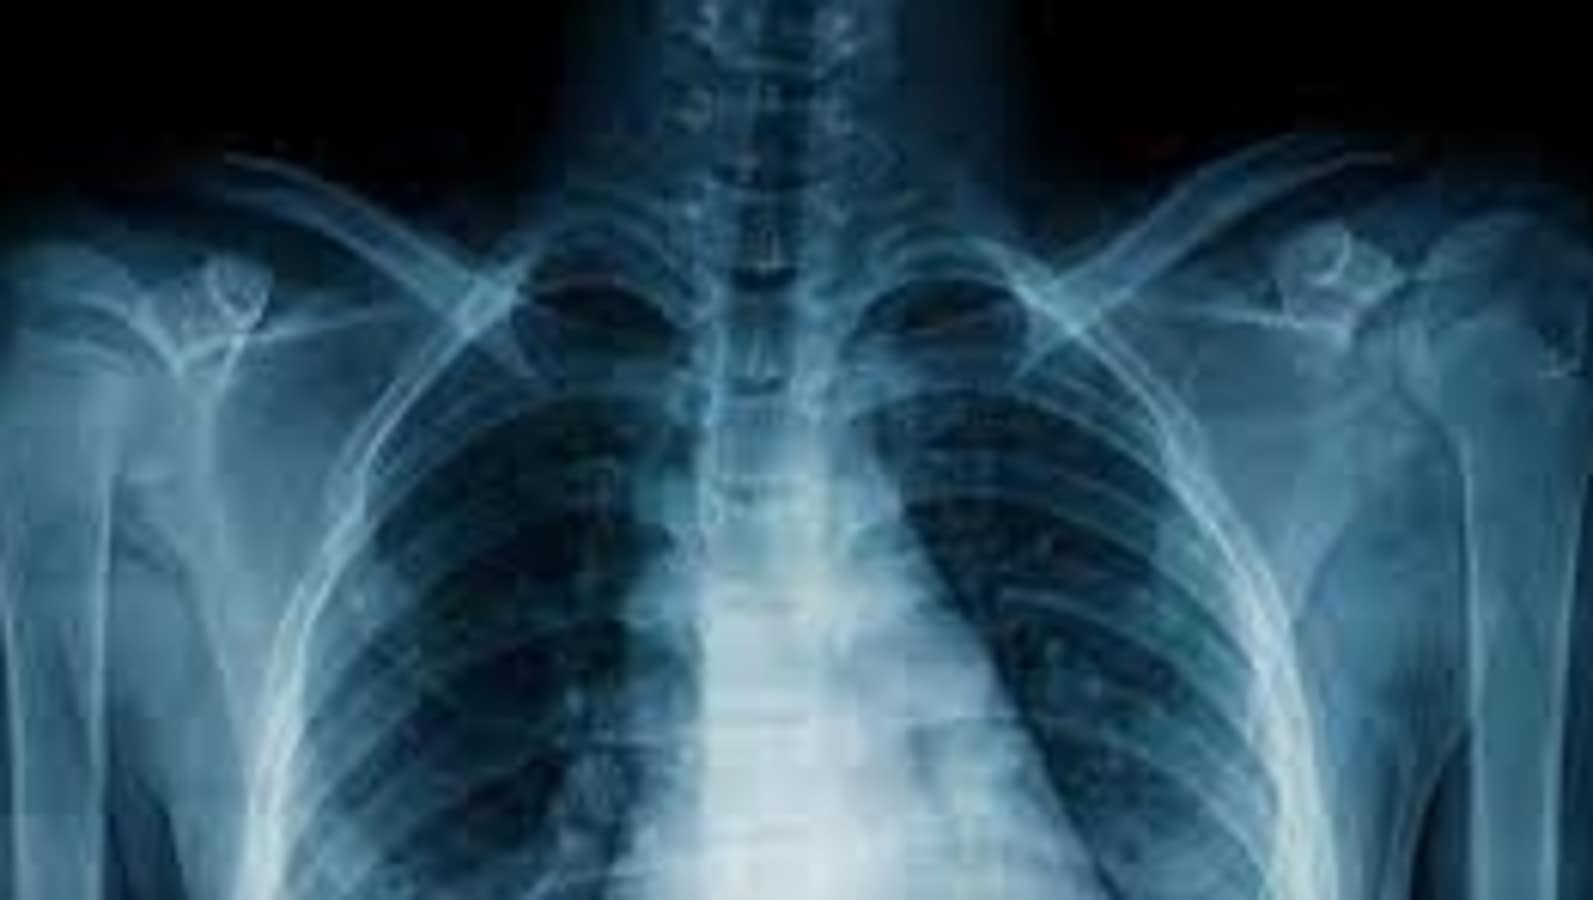

Tuberculosis, an infectious disease that mainly affects lungs, is one of the leading killer diseases that led to 1.3 million deaths in 2022. Caused by a type of bacteria called Mycobacterium tuberculosis, the disease spreads through the air when infected people cough, sneeze or spit. Tuberculosis is preventable and can be treated with a combination of antibacterial medications for a period of six to 12 months. (Also read | New insight into tuberculosis treatment: Research)

TB bacteria is also capable to attack other parts of the body be it kidney, spine, or brain. However, not all people infected with tuberculosis end up developing symptoms and many people have latent TB infection (LTBI) and TB disease. If not treated properly, TB disease can be fatal.